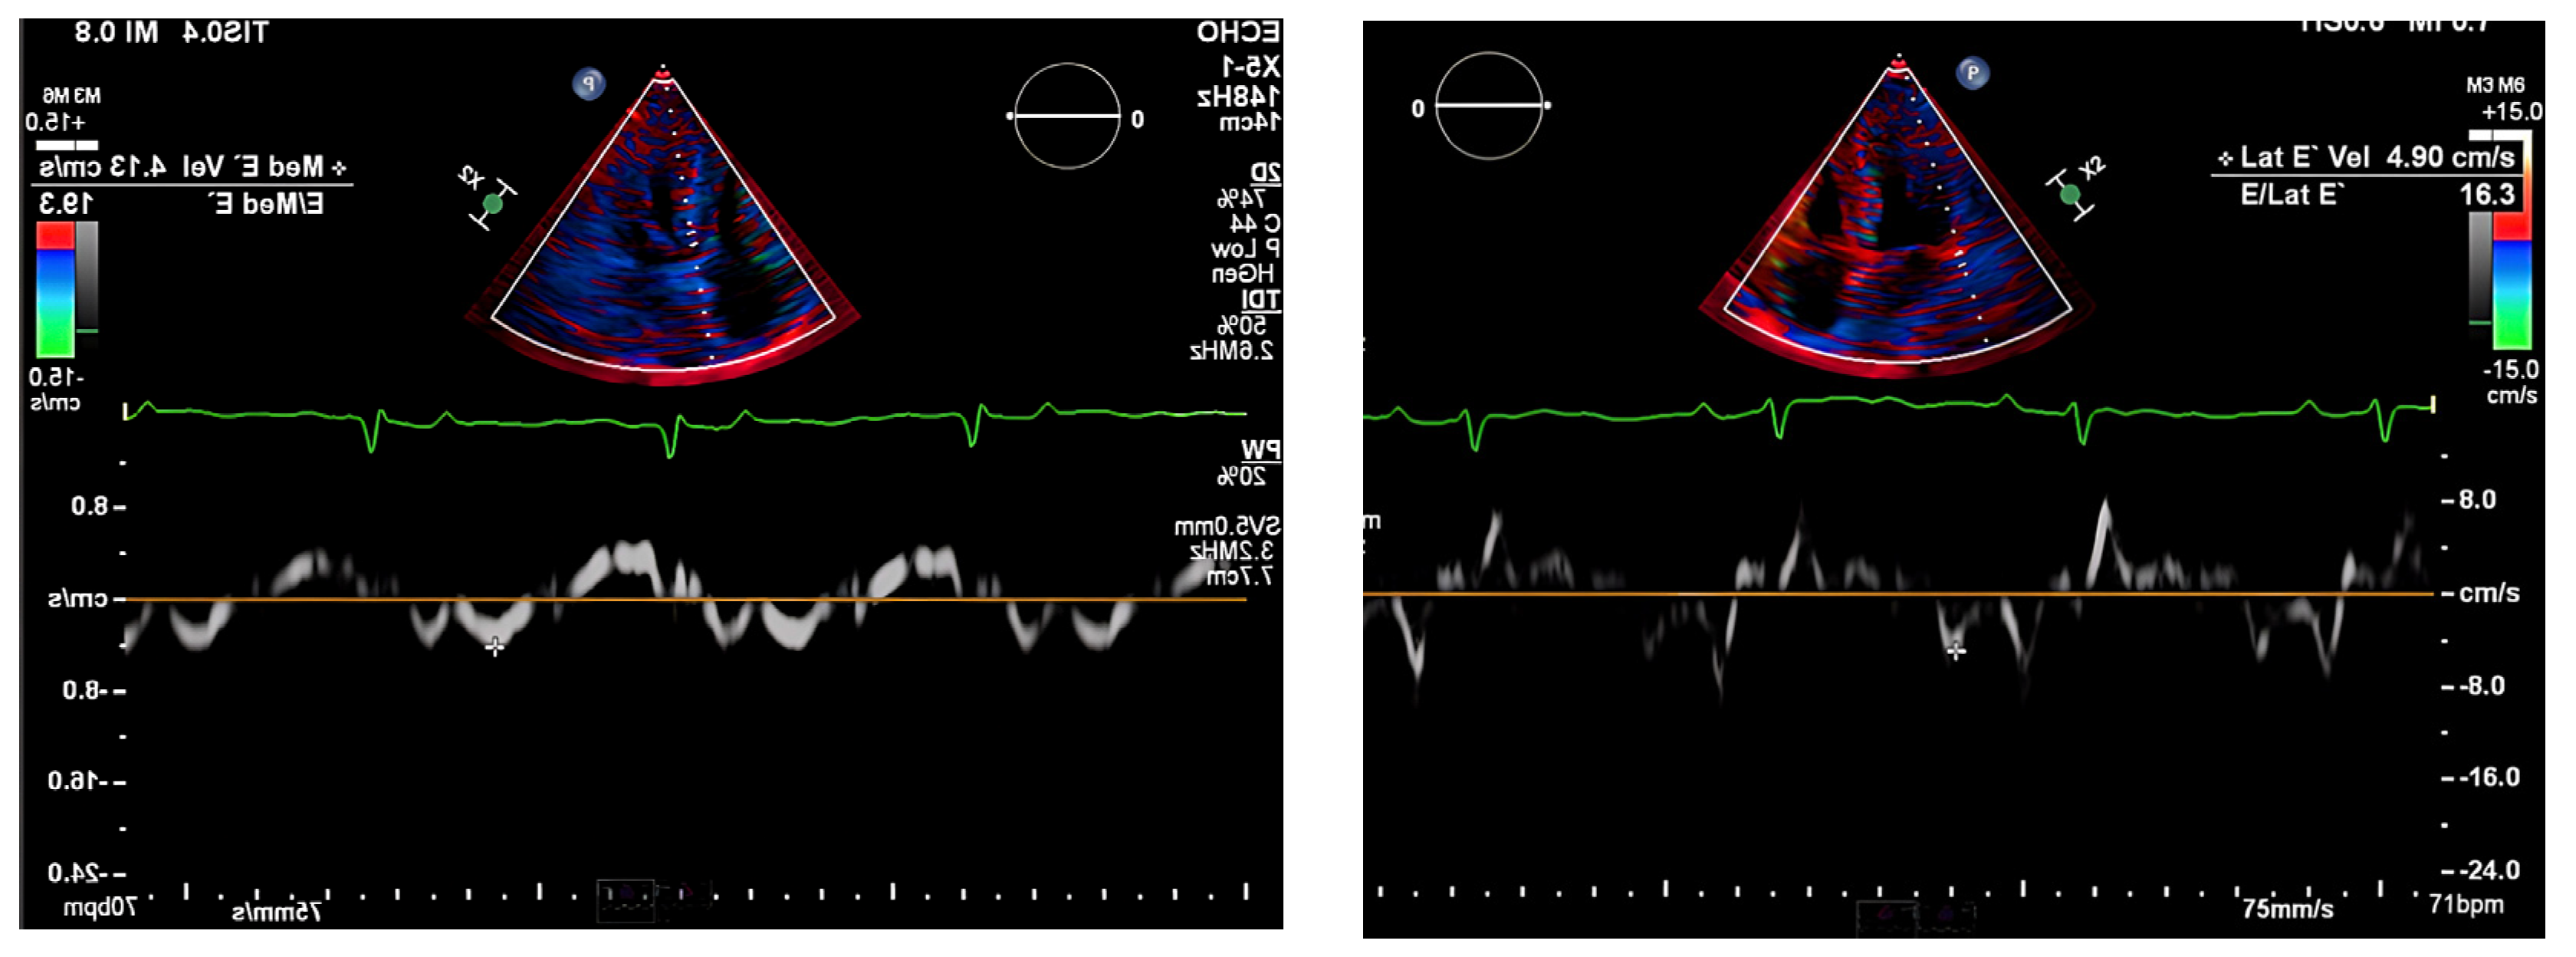

The chest radiograph did not show any acute findings. Electrocardiogram (ECG) (Figure 1) showed normal sinus rhythm with first-degree atrioventricular block, left axis deviation, and low voltage in limb leads. No prior echocardiogram (ECHO) was available, so an initial ECHO was obtained showing preserved ventricular ejection fraction (EF), moderate left ventricular hypertrophy (LVH), stage II diastolic dysfunction, and small pericardial effusion (Figure 2 and Figure 3).

Owing to the complexity and the multisystem involvement, along with the patient’s symptoms and history of GI amyloidosis, the main differential diagnosis was cardiac amyloidosis. Other differentials, such as high-output heart failure and restrictive cardiomyopathy, were considered but were less consistent with the patient’s presentation.

Figure 2. ECHO showing a discrepancy between the wall mass and electrical activity on ECG.

Figure 3. Pulse-wave Tissue Doppler ECHO showing elevated E/E′ ratio and low mitral annulus velocities suggestive of diastolic dysfunction.